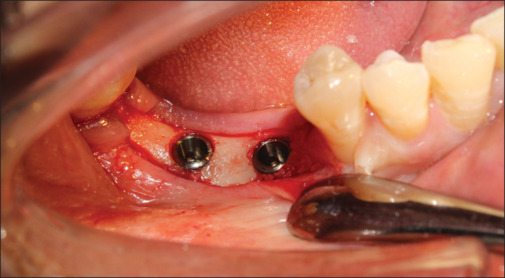

Settings and design: This research involved a sample of 15 patients who had partially dentulous mandibular arch. Within this group, a total of 30 implants were surgically placed. Specifically, each patient received two implants in the posterior region of the mandible, and the bone density in this area was classified as D2 type. In each patient, one implant was loaded with Zr abutment and the other was loaded with Ti abutment. The bone quality in the area of implant placement was Type D2. Two groups were created for this research. Each group consisted of 15 early loaded dental implants with customized Zr abutments and customized Ti abutments respectively.

Materials and methods: Hard- and soft-tissue changes were evaluated in both the groups. Evaluation of crestal bone loss (CBL) with cone beam computed tomography and SBI, PD and PESs were evaluated by various indices at 2, 4, and 6 months postloading.